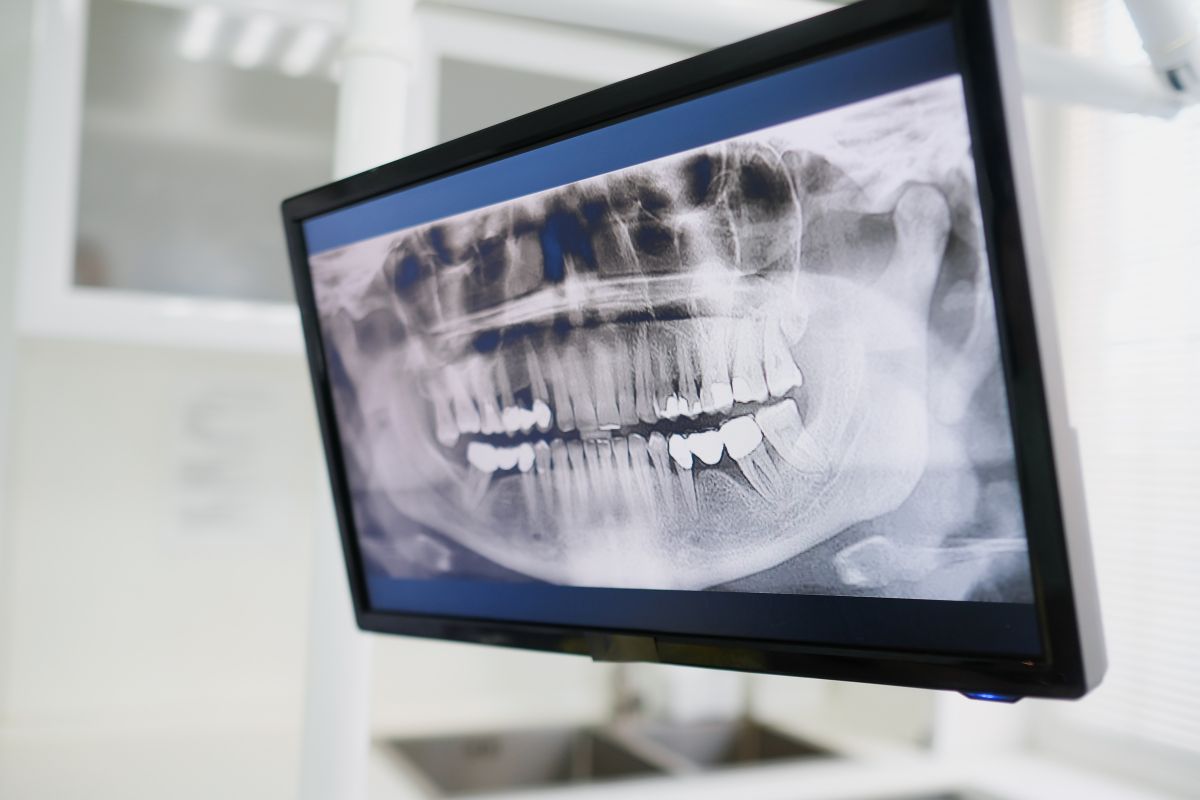

El desgaste dental es la pérdida progresiva y no traumática de los tejidos duros del diente por procesos químicos, mecánicos o fisiológicos. Factores como hábitos de bruxismo, dietas altamente ácidas y el cepillado agresivo pueden contribuir a este problema. Según Mariana Arocha y el material de SEPES, entender la causa es clave para encontrar la solución adecuada.

El desgaste excesivo puede llevar a problemas serios, como la sensibilidad dental, mordida irregular, e incluso afectar la mandíbula. Además de los problemas funcionales, la estética de la sonrisa también se ve impactada, reduciendo la confianza del paciente en sus interacciones diarias.